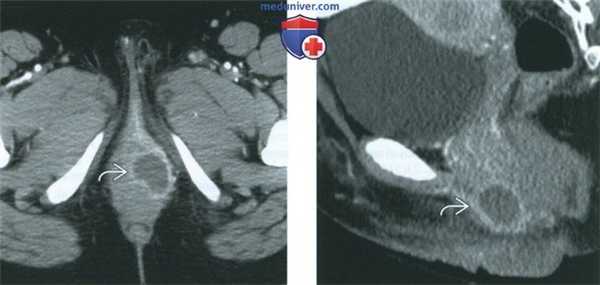

(Слева) При КТ в аксиальной плоскости с контрастным усилением в области левой заднебоковой стенки входа во влагалище выявляется кистозное образование, накапливающее контрастное вещество по периферии. Бартолинит в типичных случаях диагностируют на основании клинической картины, но исследование методами визуализации может подтвердить диагноз.

(Справа) При КТ в сагиттальной плоскости с контрастным усилением у той же пациентки визуализируется инфицированная киста бартолиновой железы с усилением сигнала по периферии. Киста располагается ниже уровня лобкового симфиза в поверхностной промежностной ямке, что отличает ее от других кист области таза.